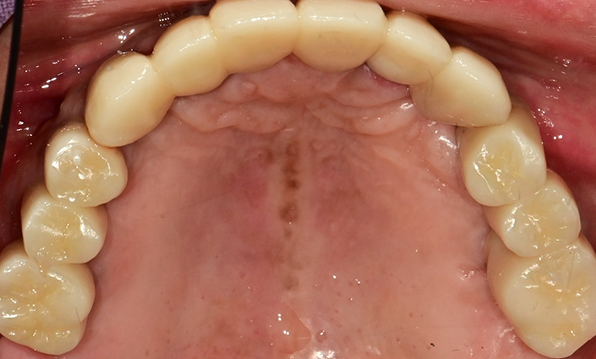

Before & After

| Before | After |